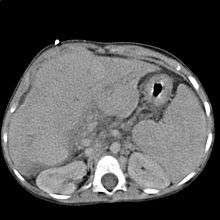

Ultrasound is routinely used in the evaluation of cirrhosis. It may show a small and nodular liver in advanced cirrhosis along with increased echogenicity with irregular appearing areas. Other findings suggestive of cirrhosis in imaging are an enlarged caudate lobe, widening of the liver fissures and enlargement of the spleen. An enlarged spleen (splenomegaly), which normally measures less than 11–12 cm in adults, is suggestive of cirrhosis with portal hypertension in the right clinical setting. Ultrasound may also screen for hepatocellular carcinoma, portal hypertension, and Budd-Chiari syndrome (by assessing flow in the hepatic vein).

Other tests performed in particular circumstances include abdominal CT and liver/bile duct MRI (MRCP).